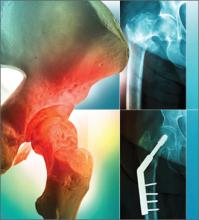

CASE After a careful review of Ms. J’s health status, radiographs of the fracture (FIGURE 1A), and consultation with an orthopedic surgeon and a geriatrician, you recommend surgery as soon as the patient is fully stabilized. Without it, she would be at high risk for urinary tract infection, pressure sores, and thromboembolism associated with long-term immobility.

The next day, Ms. J undergoes surgical fixation with a sliding hip screw (FIGURE 1B). Her Foley catheter is removed the same day, and physical therapy is begun the following day. On postoperative day 4 she is discharged to an in patient rehabilitation facility.